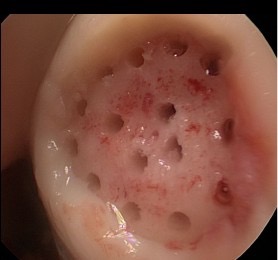

Defektareal der lateralen Femurkondyle, intraoperativer Befund während einer Arthroskopie / Gelenkspiegelung

Aufsicht auf das Defektareal nach «Mini-open» Zugang.

Nach erfolgter Präparation und durchgeführter Microfrakturierung